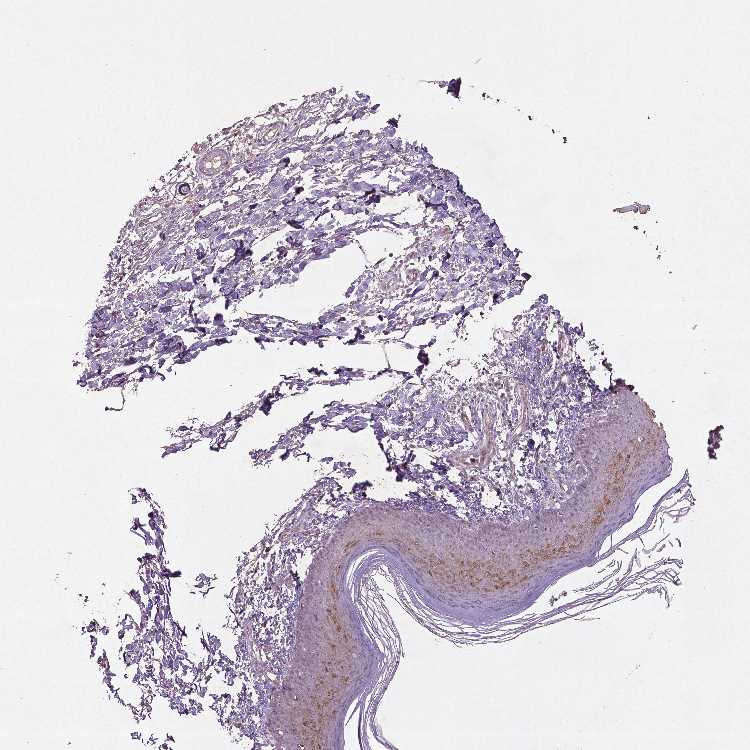

SKIN 1 - Antibody stainingi

Antibody staining in the annotated cell types in the current human tissue is reported as not detected, low, medium, or high, based on conventional immunohistochemistry profiling in selected tissues. This score is based on the combination of the staining intensity and fraction of stained cells.

Each image is clickable and will lead to virtual microscopy that enables deeper exploration of all samples and also displays staining intensity scores, fraction scores and subcellular localization as well as patient and tissue information for each sample.

Antibody CAB069425Antibody CAB080053Antibody CAB080065Antibody CAB080070Antibody CAB080081Antibody CAB080095Antibody CAB080097

Langerhans Not detectedNot detectedMediumNot detectedNot detectedNot detectedNot detected

Fibroblasts Not detectedNot detectedMediumMediumNot detectedMediumNot detected

Keratinocytes MediumMediumLowNot detectedNot detectedLowNot detected

Melanocytes Not detectedHighNot detectedMediumNot detectedMediumMedium